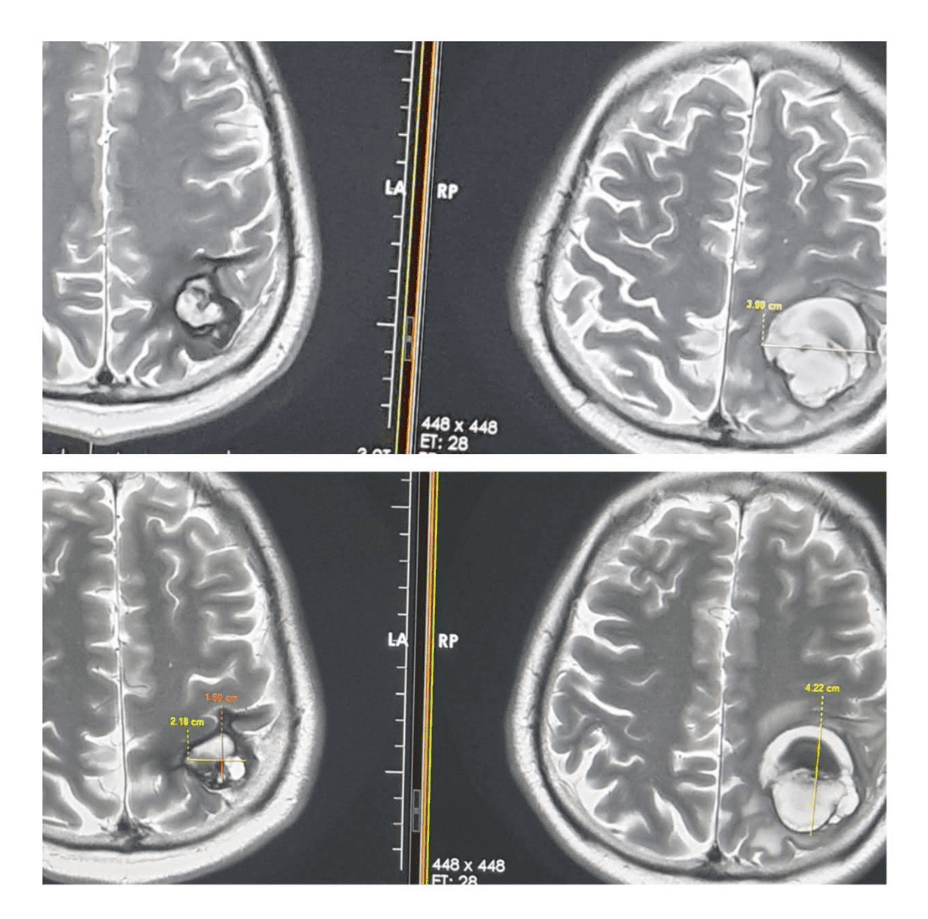

- Initial MRI (May 28, 2021):

- Tumor size: 3.98 cm x 4.22 cm

Follow-Up MRI (August 18, 2021):

- Tumor size reduced to 1.8 cm x 2.18 cm — nearly 50% reduction in dimensions and 75% reduction in volume.

- Contrast MRI Findings: Normal blood flow, no signs of bleeding or obstruction.

- Tumor Regression: 50% reduction in size and ~75% reduction in volume within 2.5 months.

- Neurological Status: Normal blood flow, no bleeding, and no need for surgical intervention.